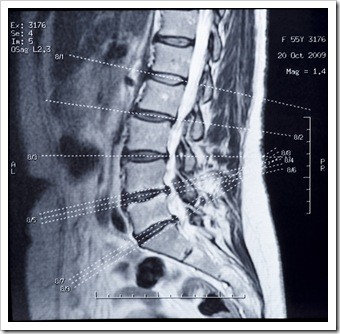

Your sciatic nerve is the longest and widest nerve in your body, and runs from the lower back, down through the buttock, and all the way into the lower leg, where it controls the muscles in that area. It also provides sensation to the thighs, legs, and the soles of the feet. When the sciatic...